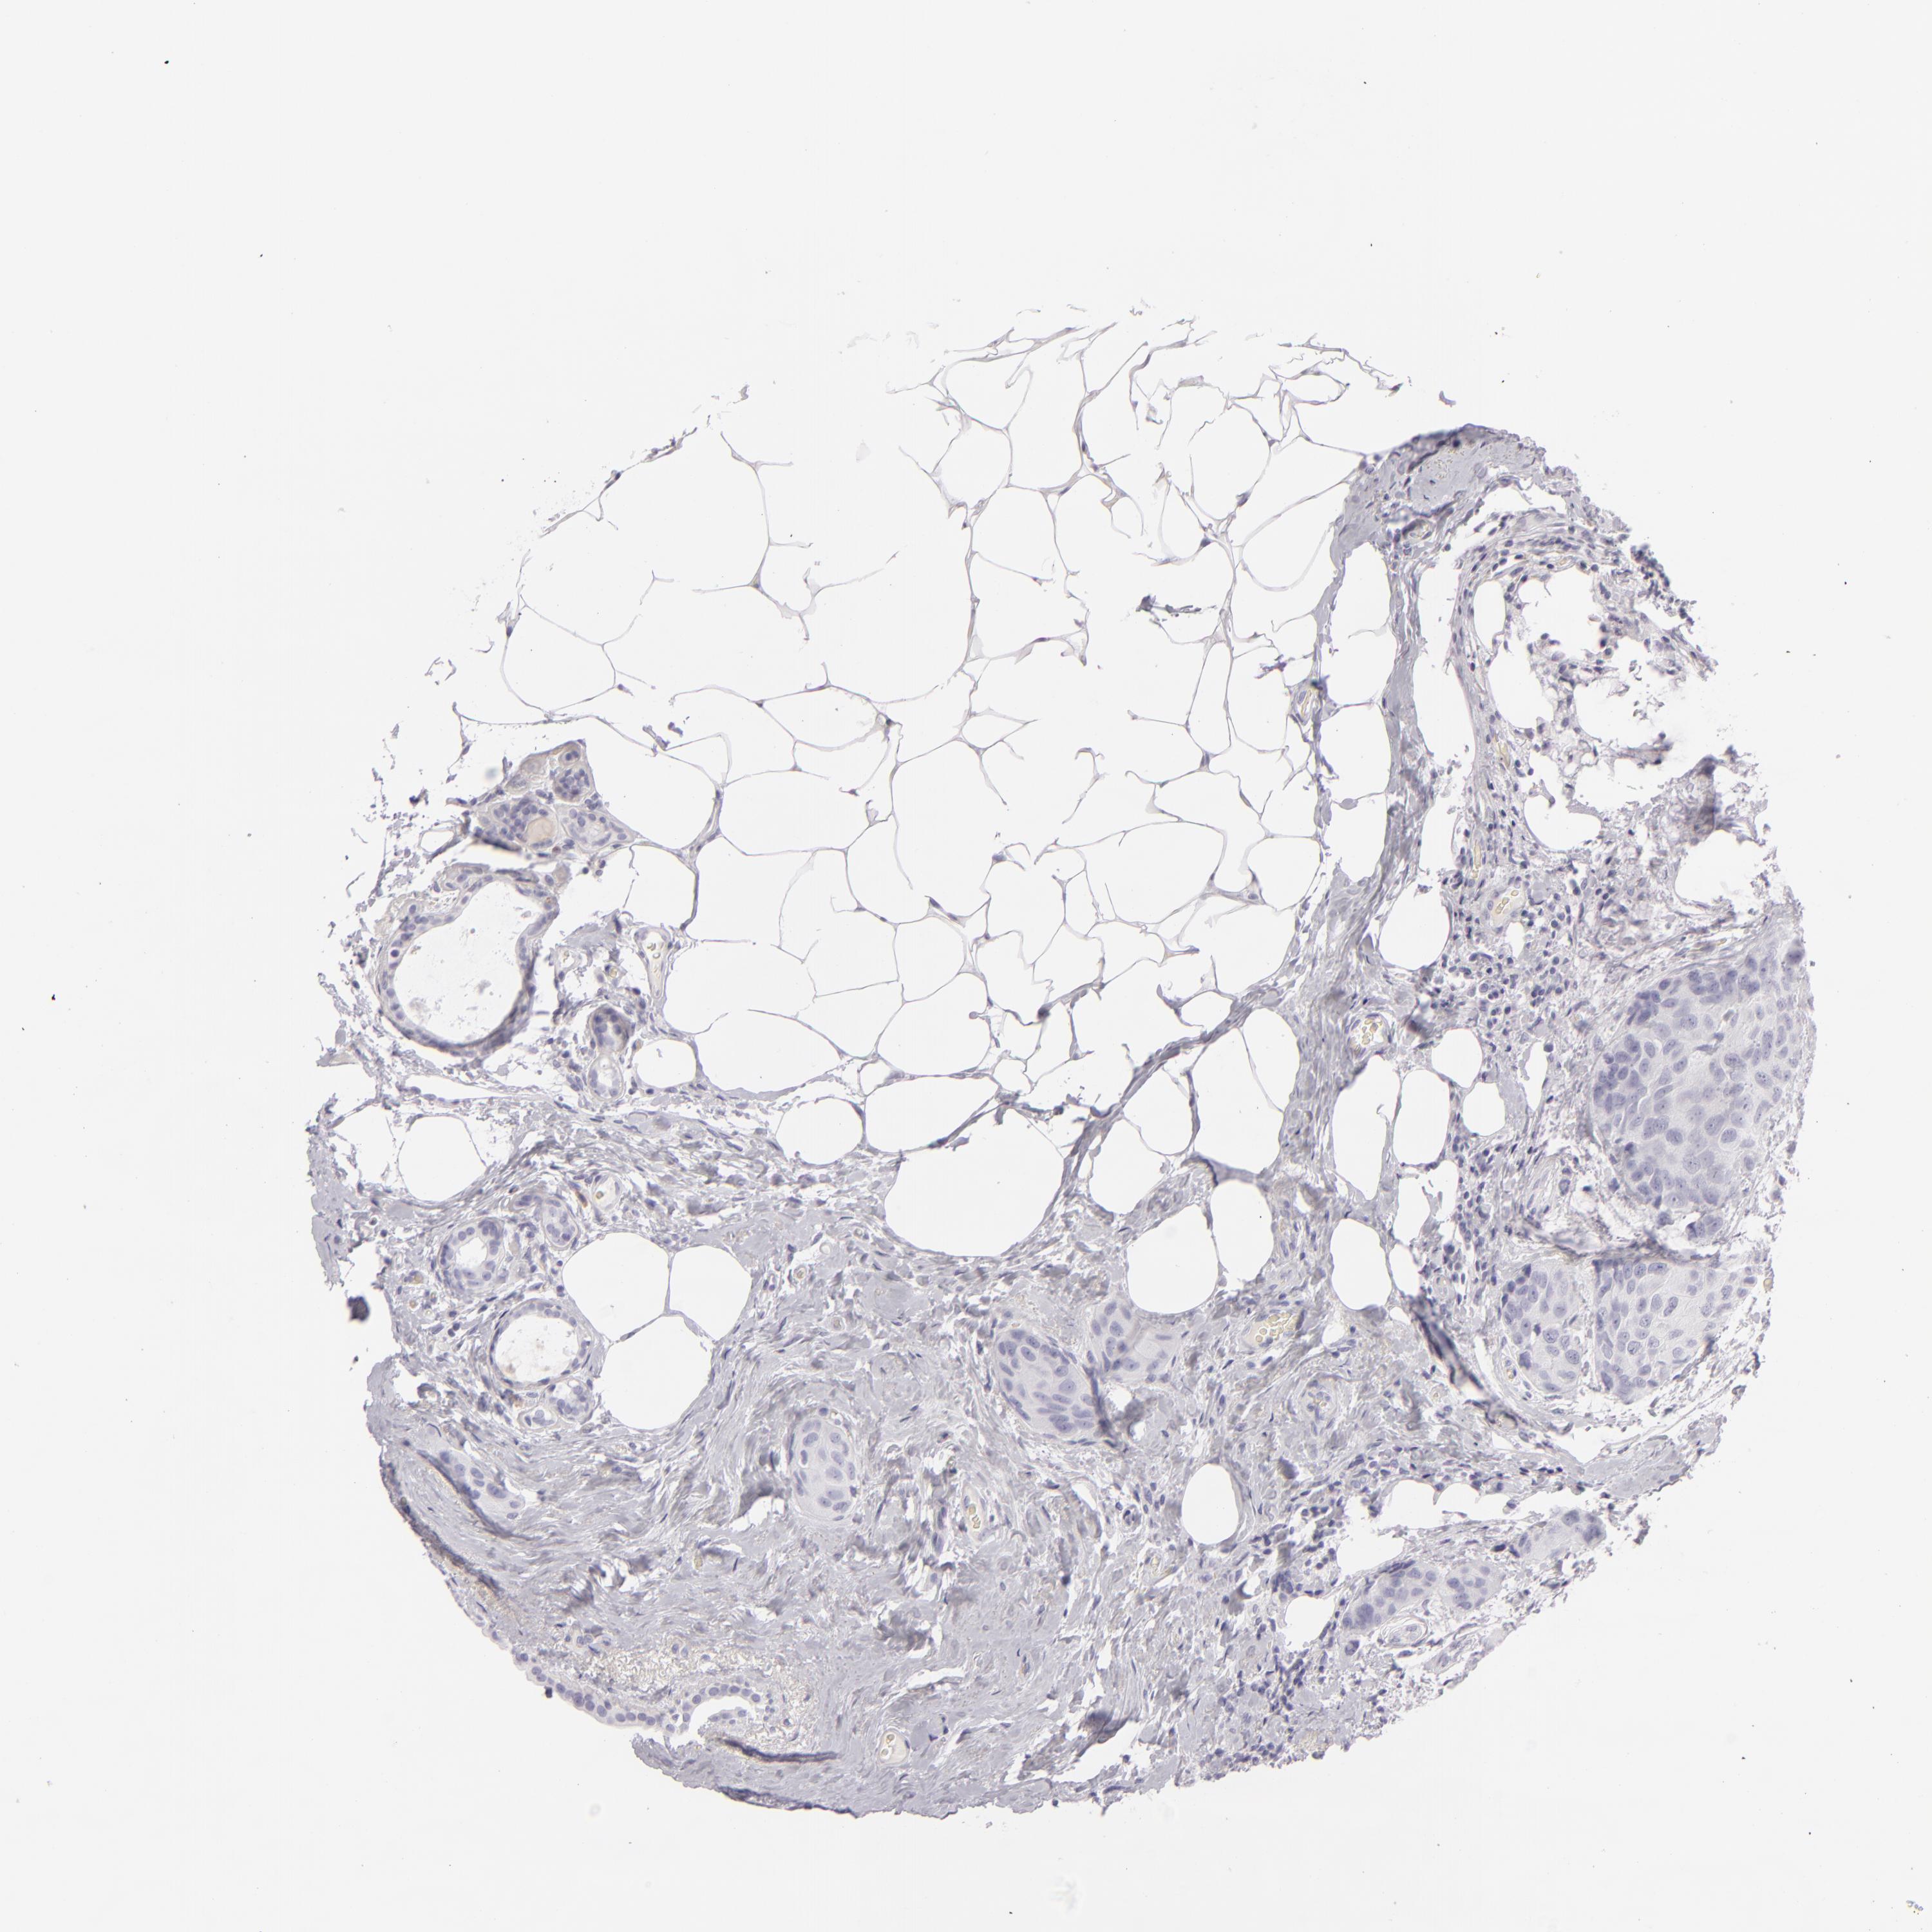

CDX2

• CDX2

CANCER BREAST CANCER Show tissue menu

Breast cancer

Human cancer